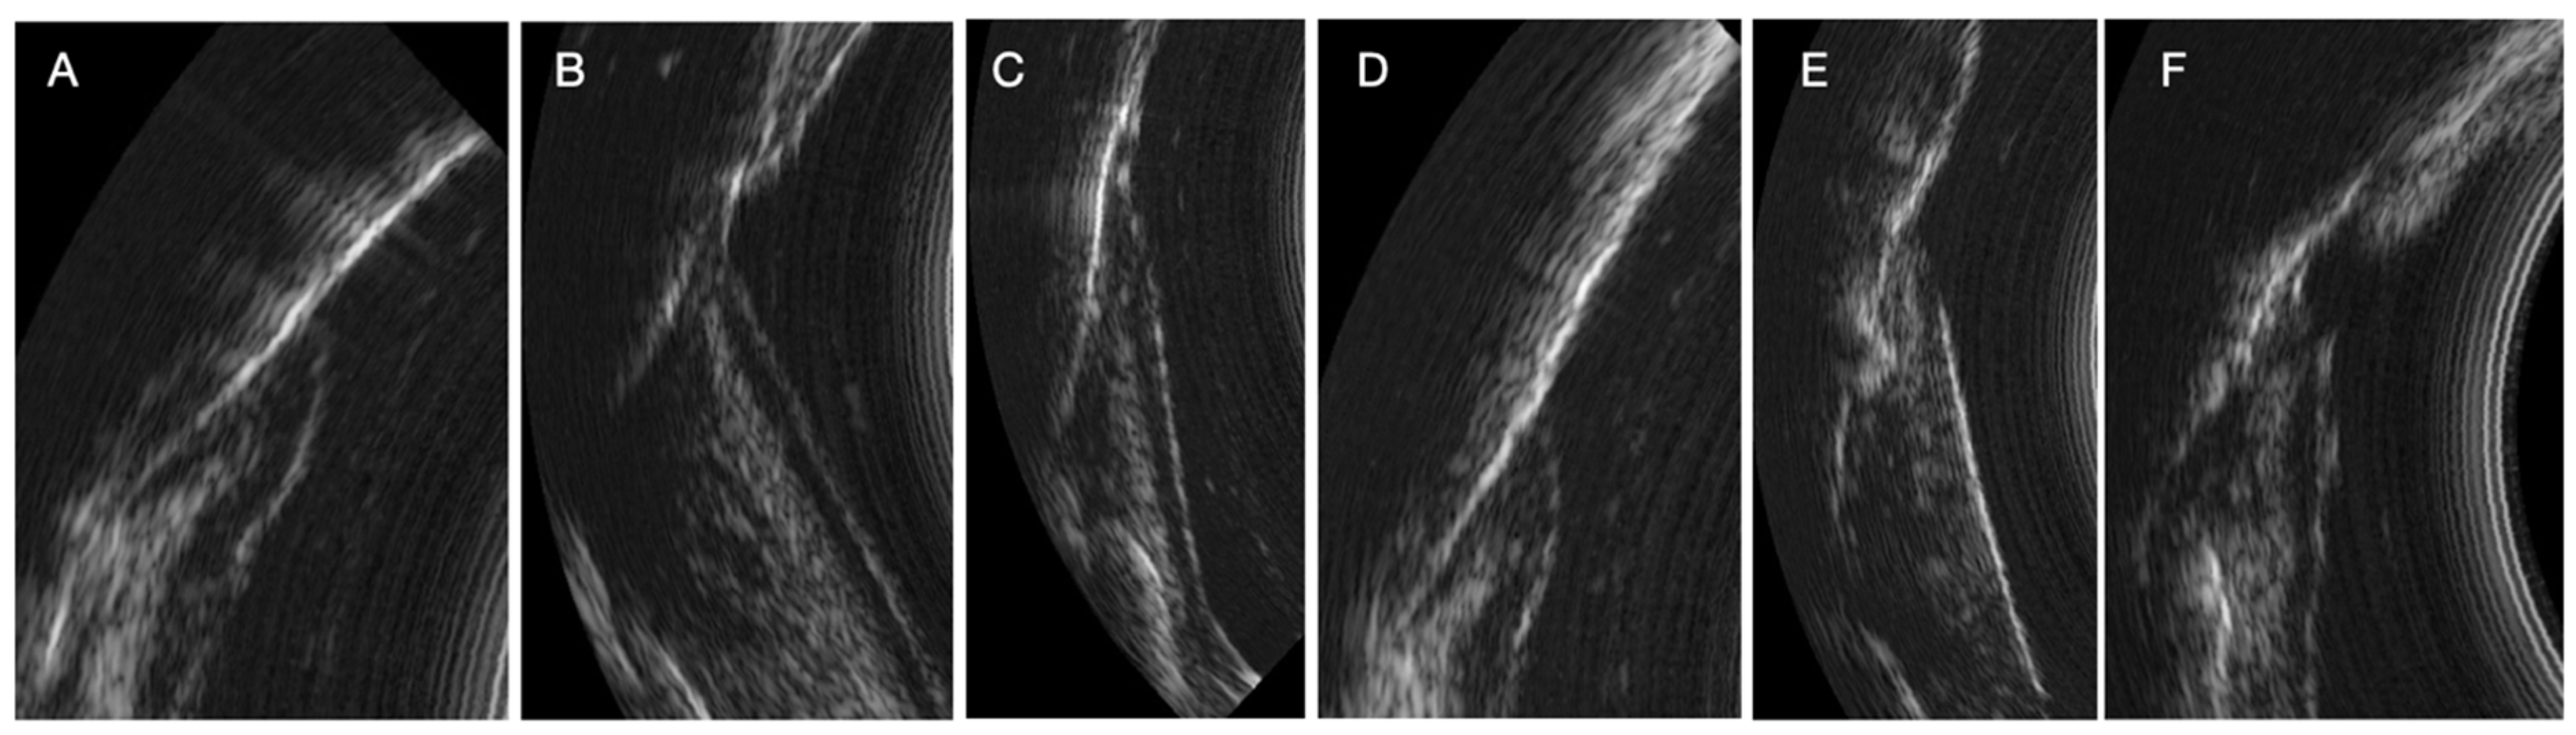

During the study, we observed many variations in ultrasound images depending on the clinical situation (inflammatory area, presence of visible calculus, edema, spontaneous bleeding, normal situation). Indeed, the images can reveal the presence of inflammation in the deep gingival tissues. Sub-gingival calculus can also be visible. The image quality is also different because of the variation in the ultrasound signal [13]. The same is true for subgingival calculus which can also be objectified on the ultrasound images. Although many of these elements appear in the image, AI currently struggles to differentiate pocket depths from surrounding structures in certain clinical contexts. These structures need to be identified and characterized for more precise training of the AI (Figure 4)

Figure 4.

Variations in periodontal ultrasound images. (A) Reference image with normal structures. (B) Presence of deep inflammation with visible connective tissue junction. (C) Presence of deep inflammation without visible connective tissue junction. (D) Presence of supragingival calculus. (E) Presence of subgingival calculus. (F) Presence of calculus above and below the gingival surface and deep inflammation.